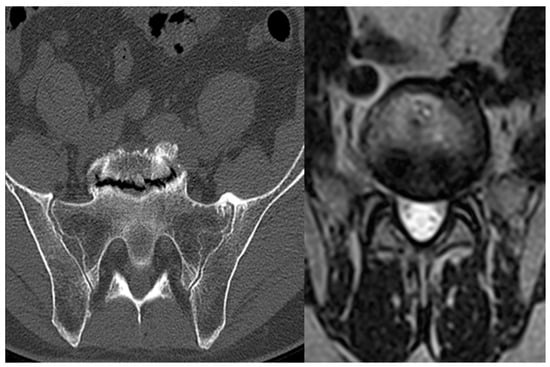

When the distance between the right and left iliac vessels is <1.5 cm, a type 2 approach must be used, i.e., lateral to the vessels (Figure 1c). This is the usual approach to accessing the L4-L5 disc, as the iliac bifurcation is usually located either at the level of this disc or even caudal to it. In the type 2 approach, the spine is accessed through the space between the psoas, laterally, and the iliac vessels, medially. Two subtypes of the type 2 approach also exist: the “narrow window” (Figure 2a), when the distance between the psoas and the iliac vessels is <2 cm, and the “wide window” (Figure 2b), when this distance is >2 cm.

Figure 2. L4-L5 approach. (a) Type 2 “narrow”; (b) Type 2 “wide”. The green arrows indicate the space available for approach.